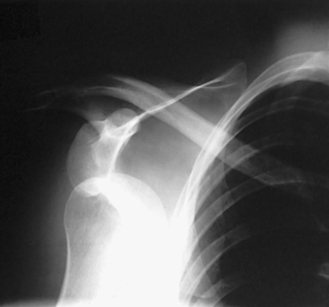

Structures shown: The scapular Y is shown on an oblique image of the shoulder. In the normal shoulder, the humeral head is directly superimposed over the junction of the Y (Fig. 5-37). In anterior (subcoracoid) dislocations, the humeral head is beneath the coracoid process (Fig. 5-38); in posterior (subacromial) dislocations, it is projected beneath the acromion process. An AP shoulder projection is shown for comparison (Fig. 5-39).

Fig. 5-38 PA oblique shoulder joint showing anterior dislocation (humeral head projected beneath coracoid process).

Fig. 5-39 AP shoulder (same patient as in Fig. 5-38).